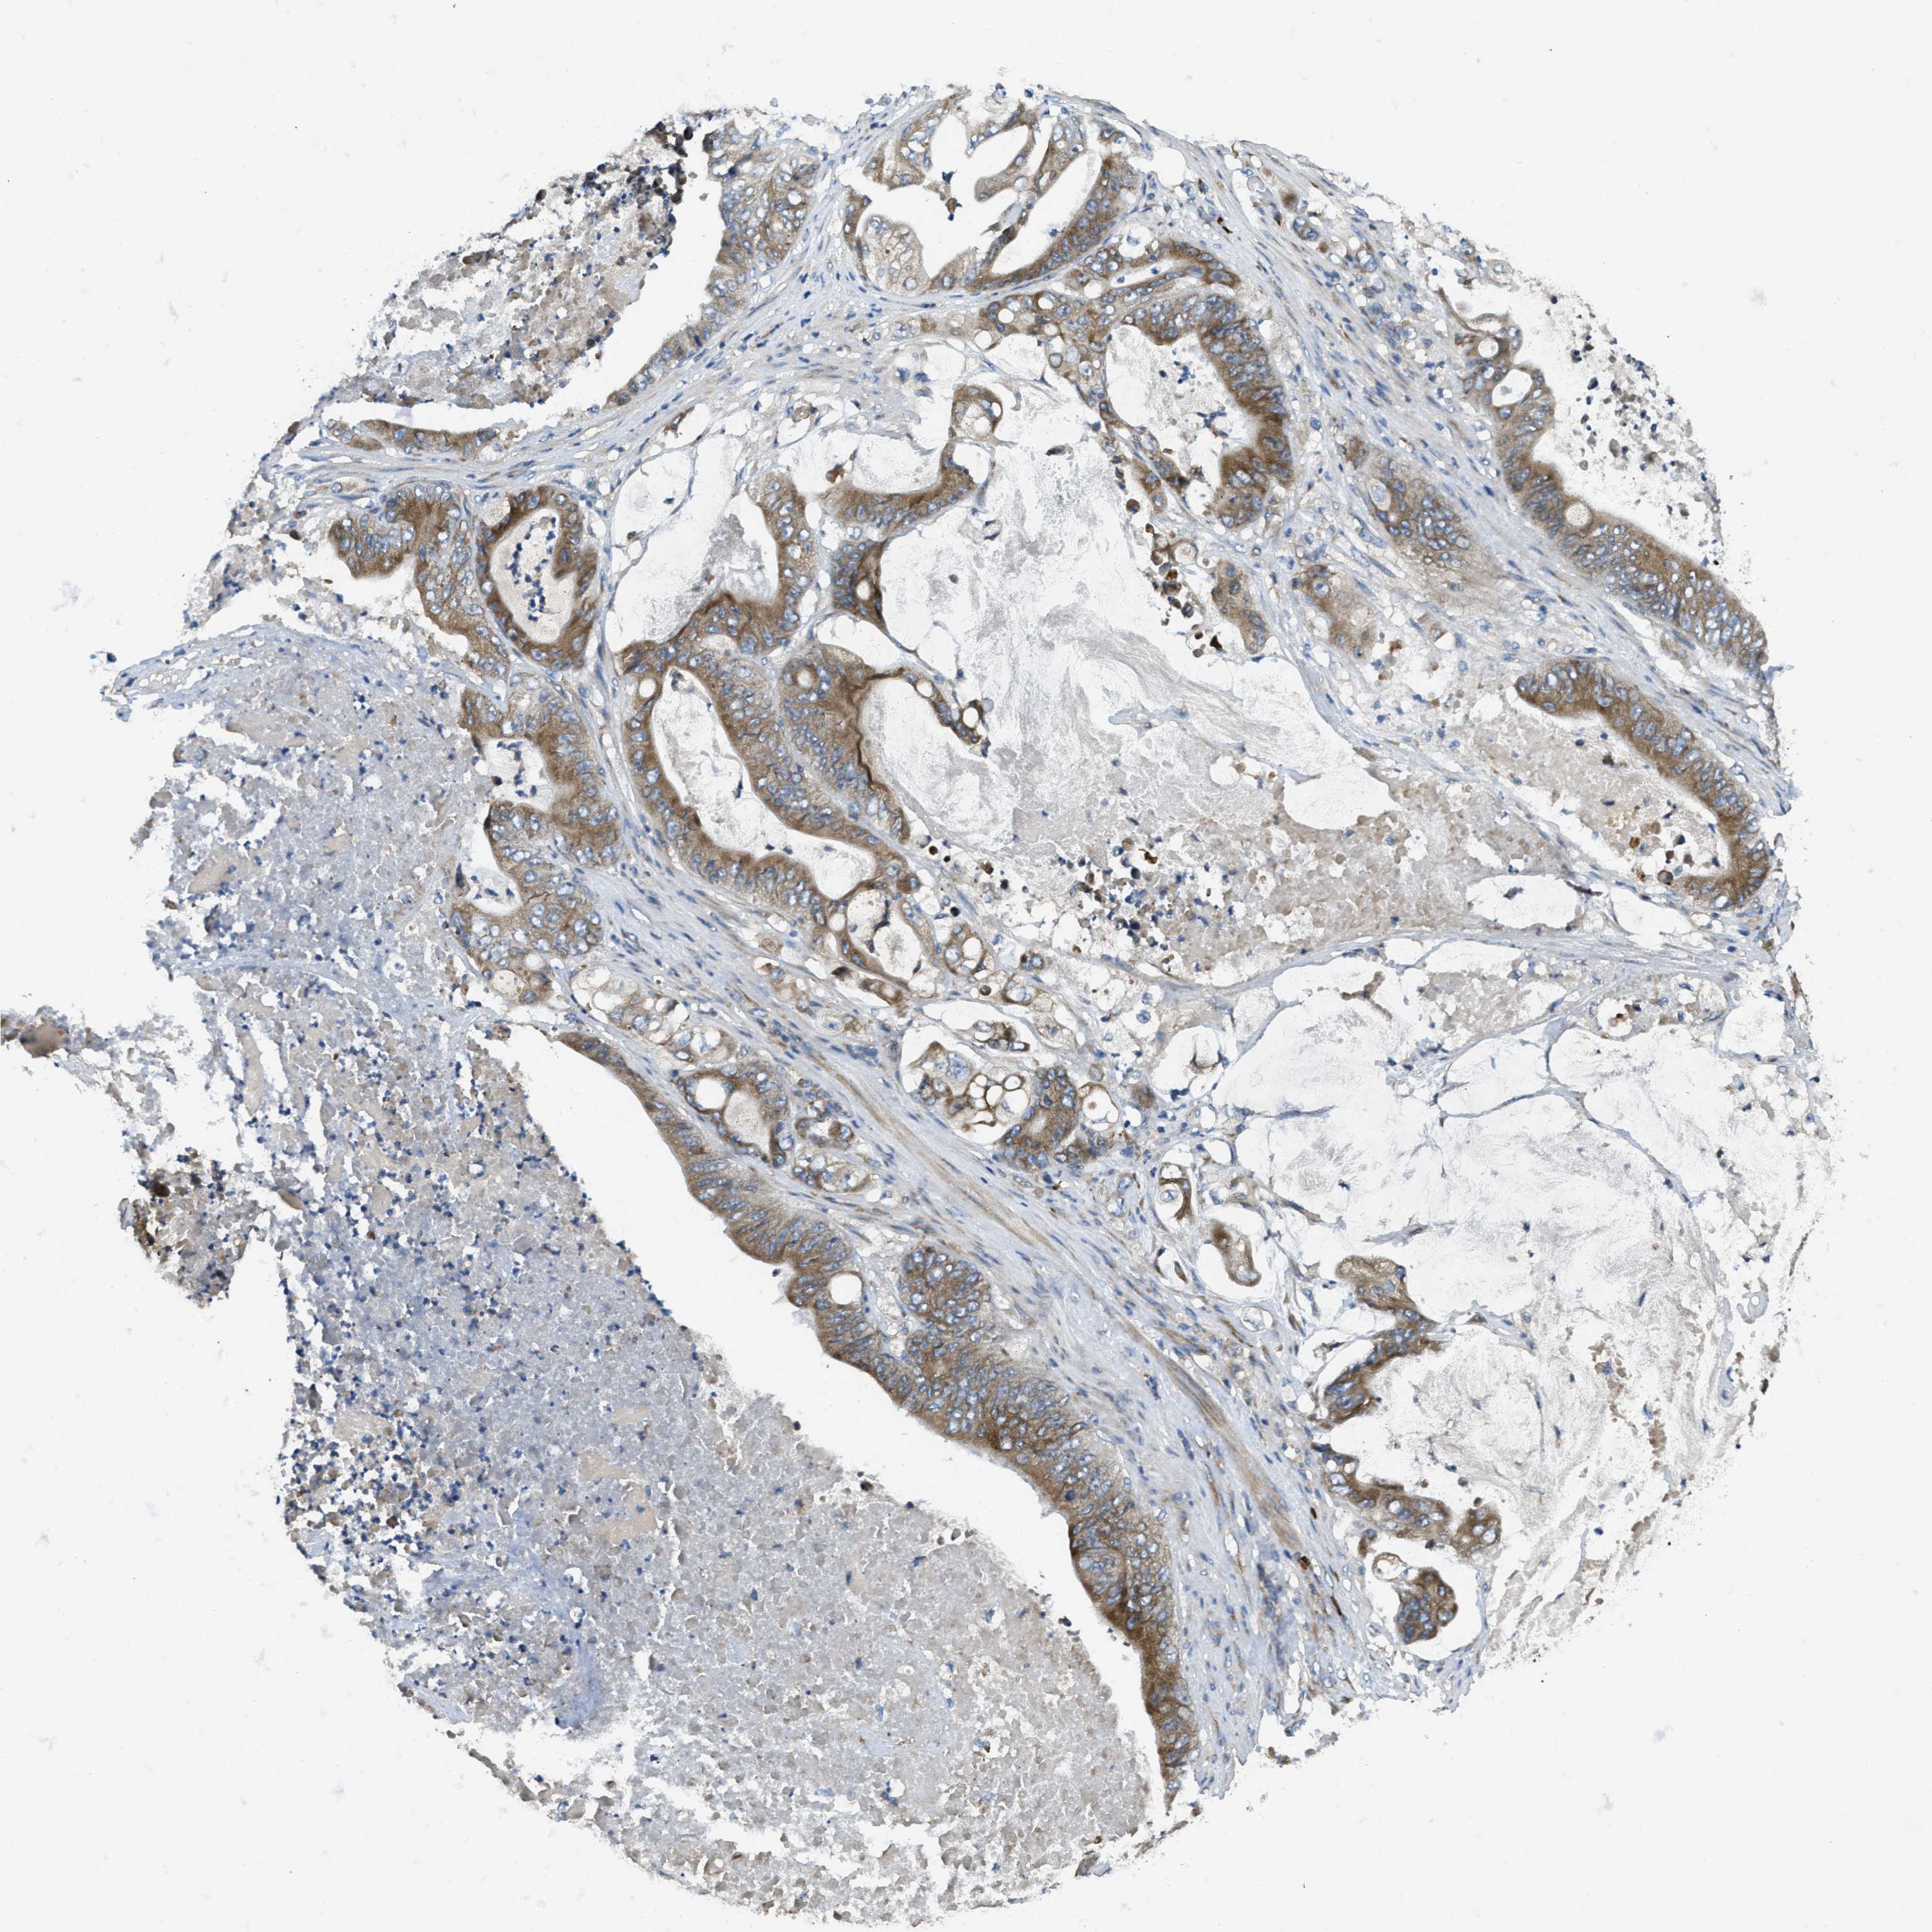

STOMACH CANCER - Protein expressioni

A mouse-over function shows sample information and annotation data. Click on an image to view it in a full screen mode. Samples can be filtered based on level of antibody staining by selecting one or several of the following categories: high, medium, low and not detected. The assay and annotation is described here.

Note that samples used for immunohistochemistry by the Human Protein Atlas do not correspond to samples in the TCGA dataset.

Antibody stainingi

Antibody staining in the annotated cell types in the current human tissue is reported as not detected, low, medium, or high, based on conventional immunohistochemistry profiling in selected tissues. This score is based on the combination of the staining intensity and fraction of stained cells.

Each image is clickable and will lead to virtual microscopy that enables deeper exploration of all samples and also displays staining intensity scores, fraction scores and subcellular localization as well as patient and tissue information for each sample.

Antibody HPA011276

Antibody HPA017062

Staining

High

Medium

Low

Not detected

Intensity

Strong

Moderate

Weak

Negative

Quantity

>75%

75%-25%

<25%

None

Location

Nuclear

Cytoplasmic/membranous

Cytoplasmic/membranous,nuclear

Adenocarcinoma, NOS

Adenocarcinoma, High grade